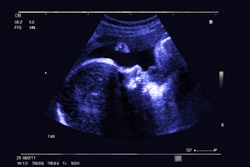

We're also highlighting a case series presented at the RANZCR meeting that shows how CT plays a role in identifying ovarian torsion -- an uncommon but serious condition that involves the twisting of the ovarian vascular pedicle -- as well as research conducted by a team in Turkey that suggests that music lowers anxiety and pain for women undergoing mammography.